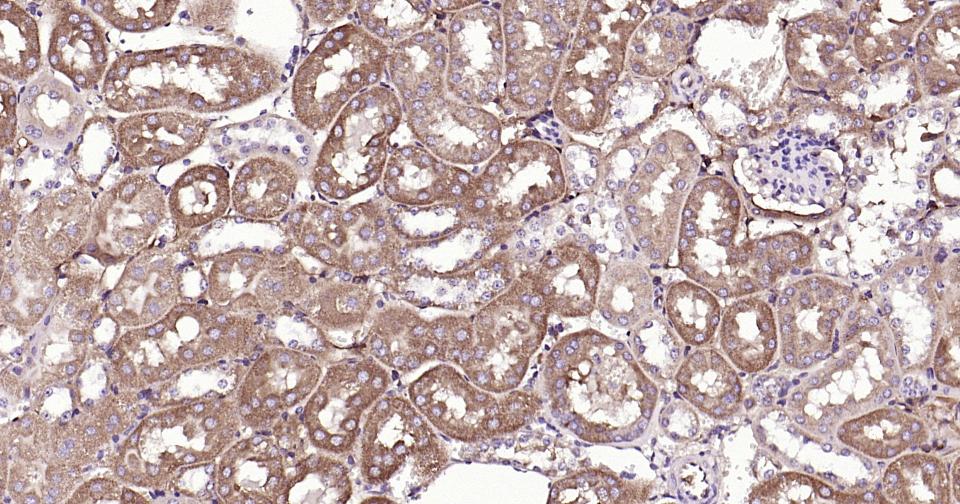

| 应用 | 已检合格种属 | 预测种属 | 推荐稀释比例 |

|---|---|---|---|

| IHC-P | Human, Mouse, Rat | 1:100-500 | |

| IHC-F | Human, Mouse, Rat | 1:100-500 | |

| IF | Human, Mouse, Rat | 1:100-500 |

交叉反应: Human, Mouse, Rat